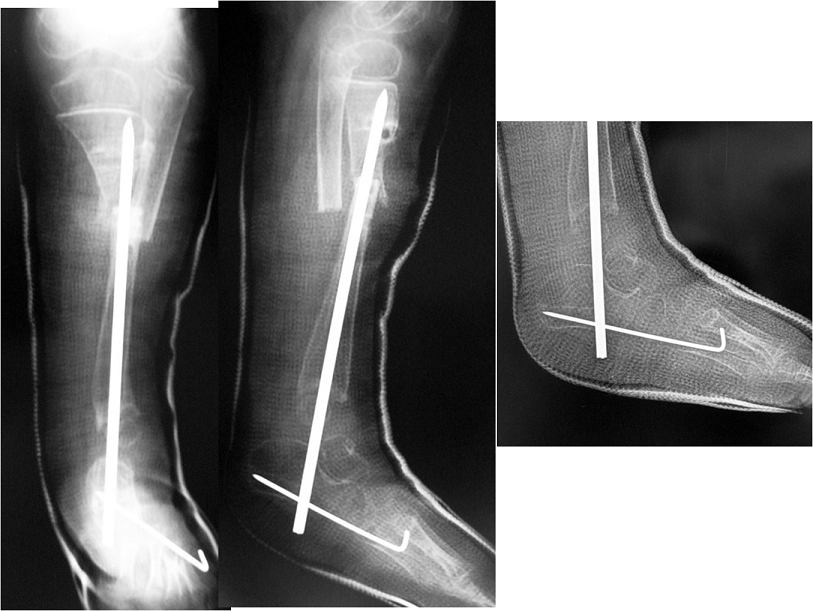

Congenital Pediatric Orthopedic DiseasesDec 30, 2021 | Case ExamplesBilateral GKD Case 1 Bilateral GKD Case 2 Bilateral GKD Case 3 Bilateral GKD Case 4 Congenital Clubfoot Fibuler Hemimeli Tibial Hemimeli PFFD